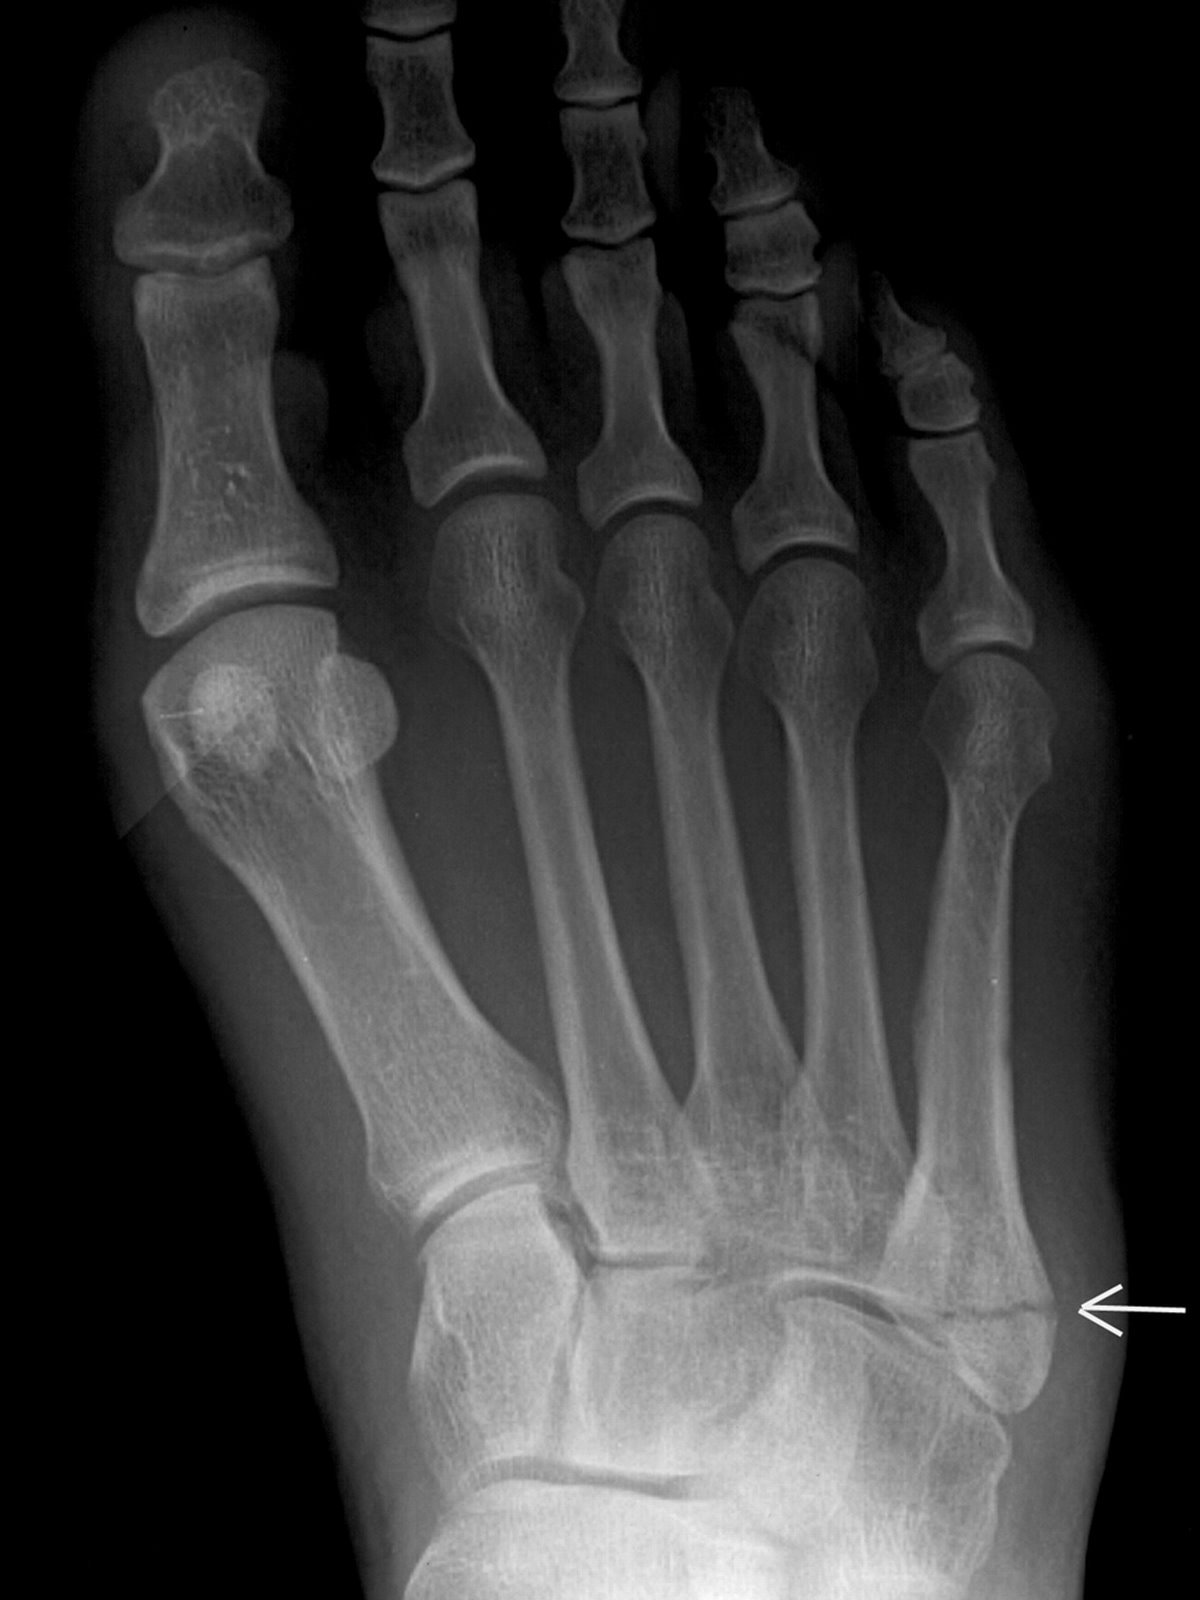

Jones+Fracture (image)

Jones Fracture (XRay) radRounds Radiology Network

The jones fracture Radiology the Best Medical